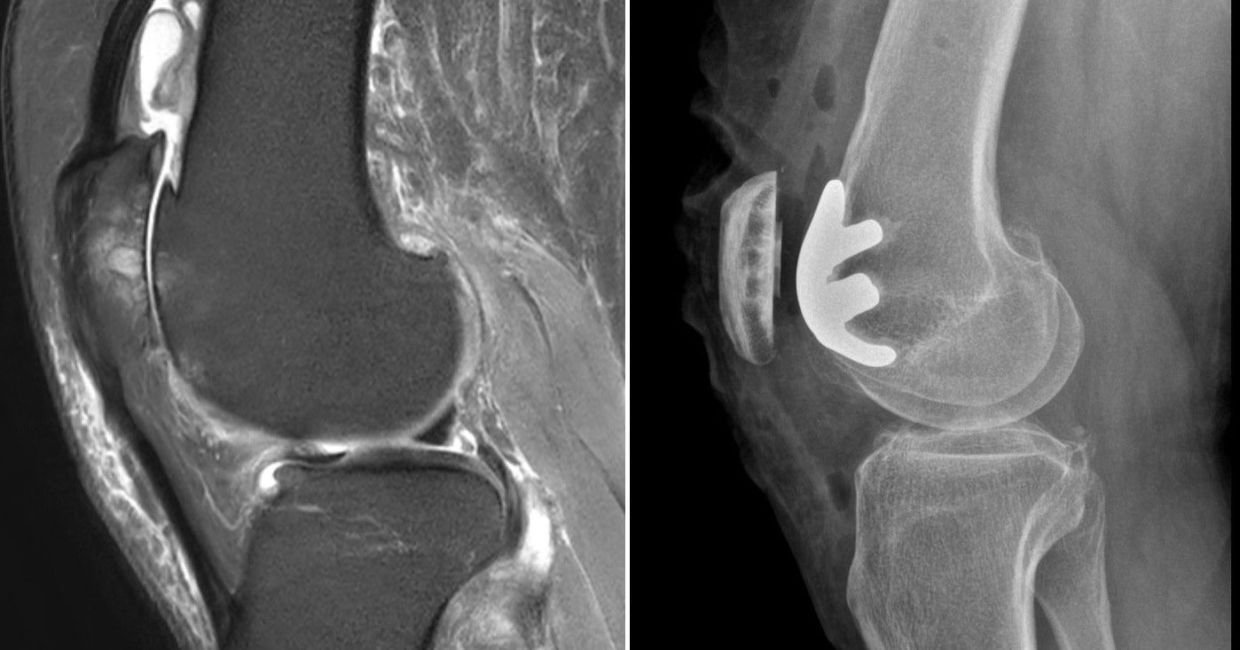

One such example is the surgical management of severe isolated patellofemoral osteoarthritis (PFOA). This particular pattern of arthritis is rare and conventional TKR may lead to poor functional outcomes as the normal parts of the joint and ligaments are unnecessarily replaced. Robots now empower more surgeons to perform a limited patellofemoral replacement, previously not widely done due to the technically demanding nature of this surgery done conventionally.

X-ray and MRI images showing severe isolated patellofemoral osteoarthritis. The remaining compartments of the knee are otherwise unaffected. Robotic limited patellofemoral replacement was first performed in Malaysia, with early functional recovery for the patient.